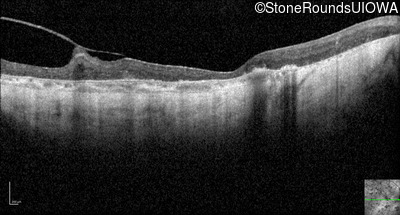

Optical Coherence Tomography - Right - Light Perception

Exemplar / OCT Stack